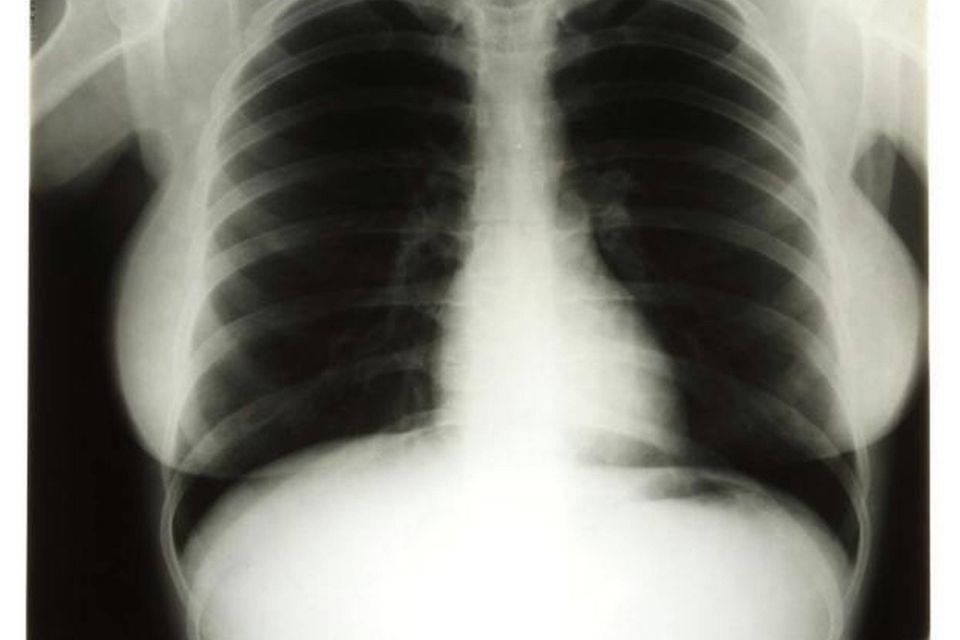

Røntgenbilleder af Marilyn Monroe er solgt til en pris, der er 15 gange højere end forventet.

Om det er Marilyn Monroes lunger eller omridset af hendes barm, der er eftertragtet, må man selv tænke sig til.

Tre røntgenbilleder af den legendariske skuespillers frontparti er på en auktion blevet solgt for 272.000 kr., skriver nyhedsbureauet AP. Det var langt højere, end sælgerne havde forventet, selvom de fleste af Marilyn Monroes ejendele som regel går som varmt brød.

Røntgenbillederne af Marilyn Monroes lunger er fra 1954, hvor hun var indlagt på hospitalet pga. mavesmerter.